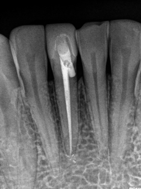

All canals cleaned and shaped?

Did you know there is not a standard number of canals for each tooth? So finding all the canals can be a challenge. Did the dentist treat each of the canals of your tooth or did he/she miss one. Missing a canal can leave an opening for future infections and require another procedure in the future.

Canals cleaned and shaped to the apex?

The filling should go to the tip of your root. Not filling enough (under-fill) can leave space for harmful bacteria to grow. A filling that goes beyond the root tip (over-fill) can cause damage to the bone, sinus, or even nerve damage in severe cases. Over or under filling increases the chances that you'll need to have another procedure down the road.